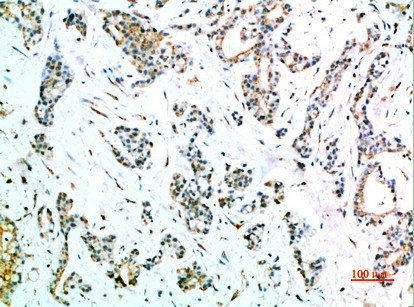

Immunohistochemical analysis of paraffin-embedded human-stomach-cancer, antibody was diluted at 1:200